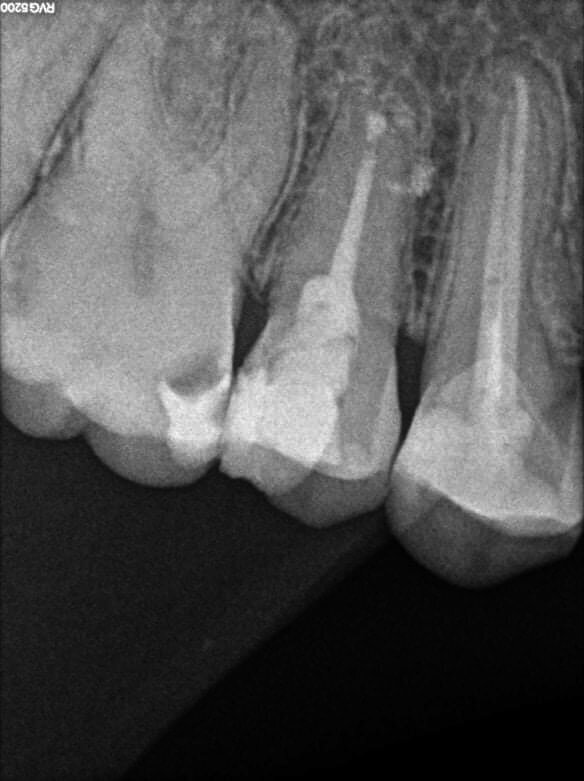

A 63 year old female patient, with a non-contributory medical history, consulted owing to moderate pain associated with her previously treated mandibular left first molar. CBCT revealed that a mesiobuccal canal had being missed during initial treatment, that the mesial and distal roots were affected by an apical lesion, and that the cortical buccal bone was intact.

Retreatment was done in two appointments, and calcium hydroxide was used as the intra-canal dressing after removing the previous filling material and cleaning and shaping three canals. After one week, root canal therapy was completed. Two months later, symptoms persisted and clinical examination revealed pain on vertical percussion; periodontal probing depth and mobility were within normal limits. CBCT revealed no signs of bone healing (Figs. 1a–c). The diagnosis for tooth #36 was previously treated symptomatic periapical periodontitis, and the treatment of choice was guided EMS.